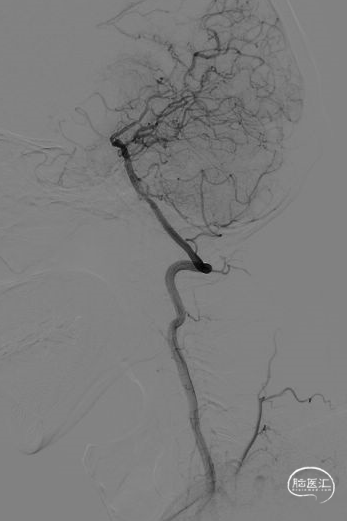

弓造影:主动脉弓II型。

左椎造影:左侧椎动脉V3-4走形迂曲,基底动脉扩张延长(分叉高度3级,偏移度2级),管腔光滑,未见明显狭窄斑块。右侧大脑后动脉通过软脑膜向右侧大脑前动脉及中动脉部分代偿,代偿2级。左侧胚胎型大脑后动脉。

左颈造影:左侧颈内动脉、左侧大脑前动脉走形迂曲。左侧颈内动脉、大脑中动脉、大脑前动脉管腔基本光滑,未见明显血管狭窄斑块。前交通开放,左侧大脑前动脉通过前交通动脉向右侧大脑前动脉及中动脉部分代偿供血,代偿2级。

右颈造影:右侧颈内动脉走形迂曲,右侧大脑前动脉走形严重迂曲,管腔光滑,未见明显血管狭窄斑块。右侧大脑中动脉M1段次全闭塞,右侧大脑前动脉通过软脑膜动脉向右侧大脑中动脉供血区代偿供血,右侧颈外动脉通过颞浅动脉向右侧大脑中动脉供血区代偿供血,代偿2级。

右椎造影:右侧椎动脉走形尚可,管腔光滑,未见明显血管狭窄斑块。

2、DSA:右侧大脑中动脉M1段次全闭塞。